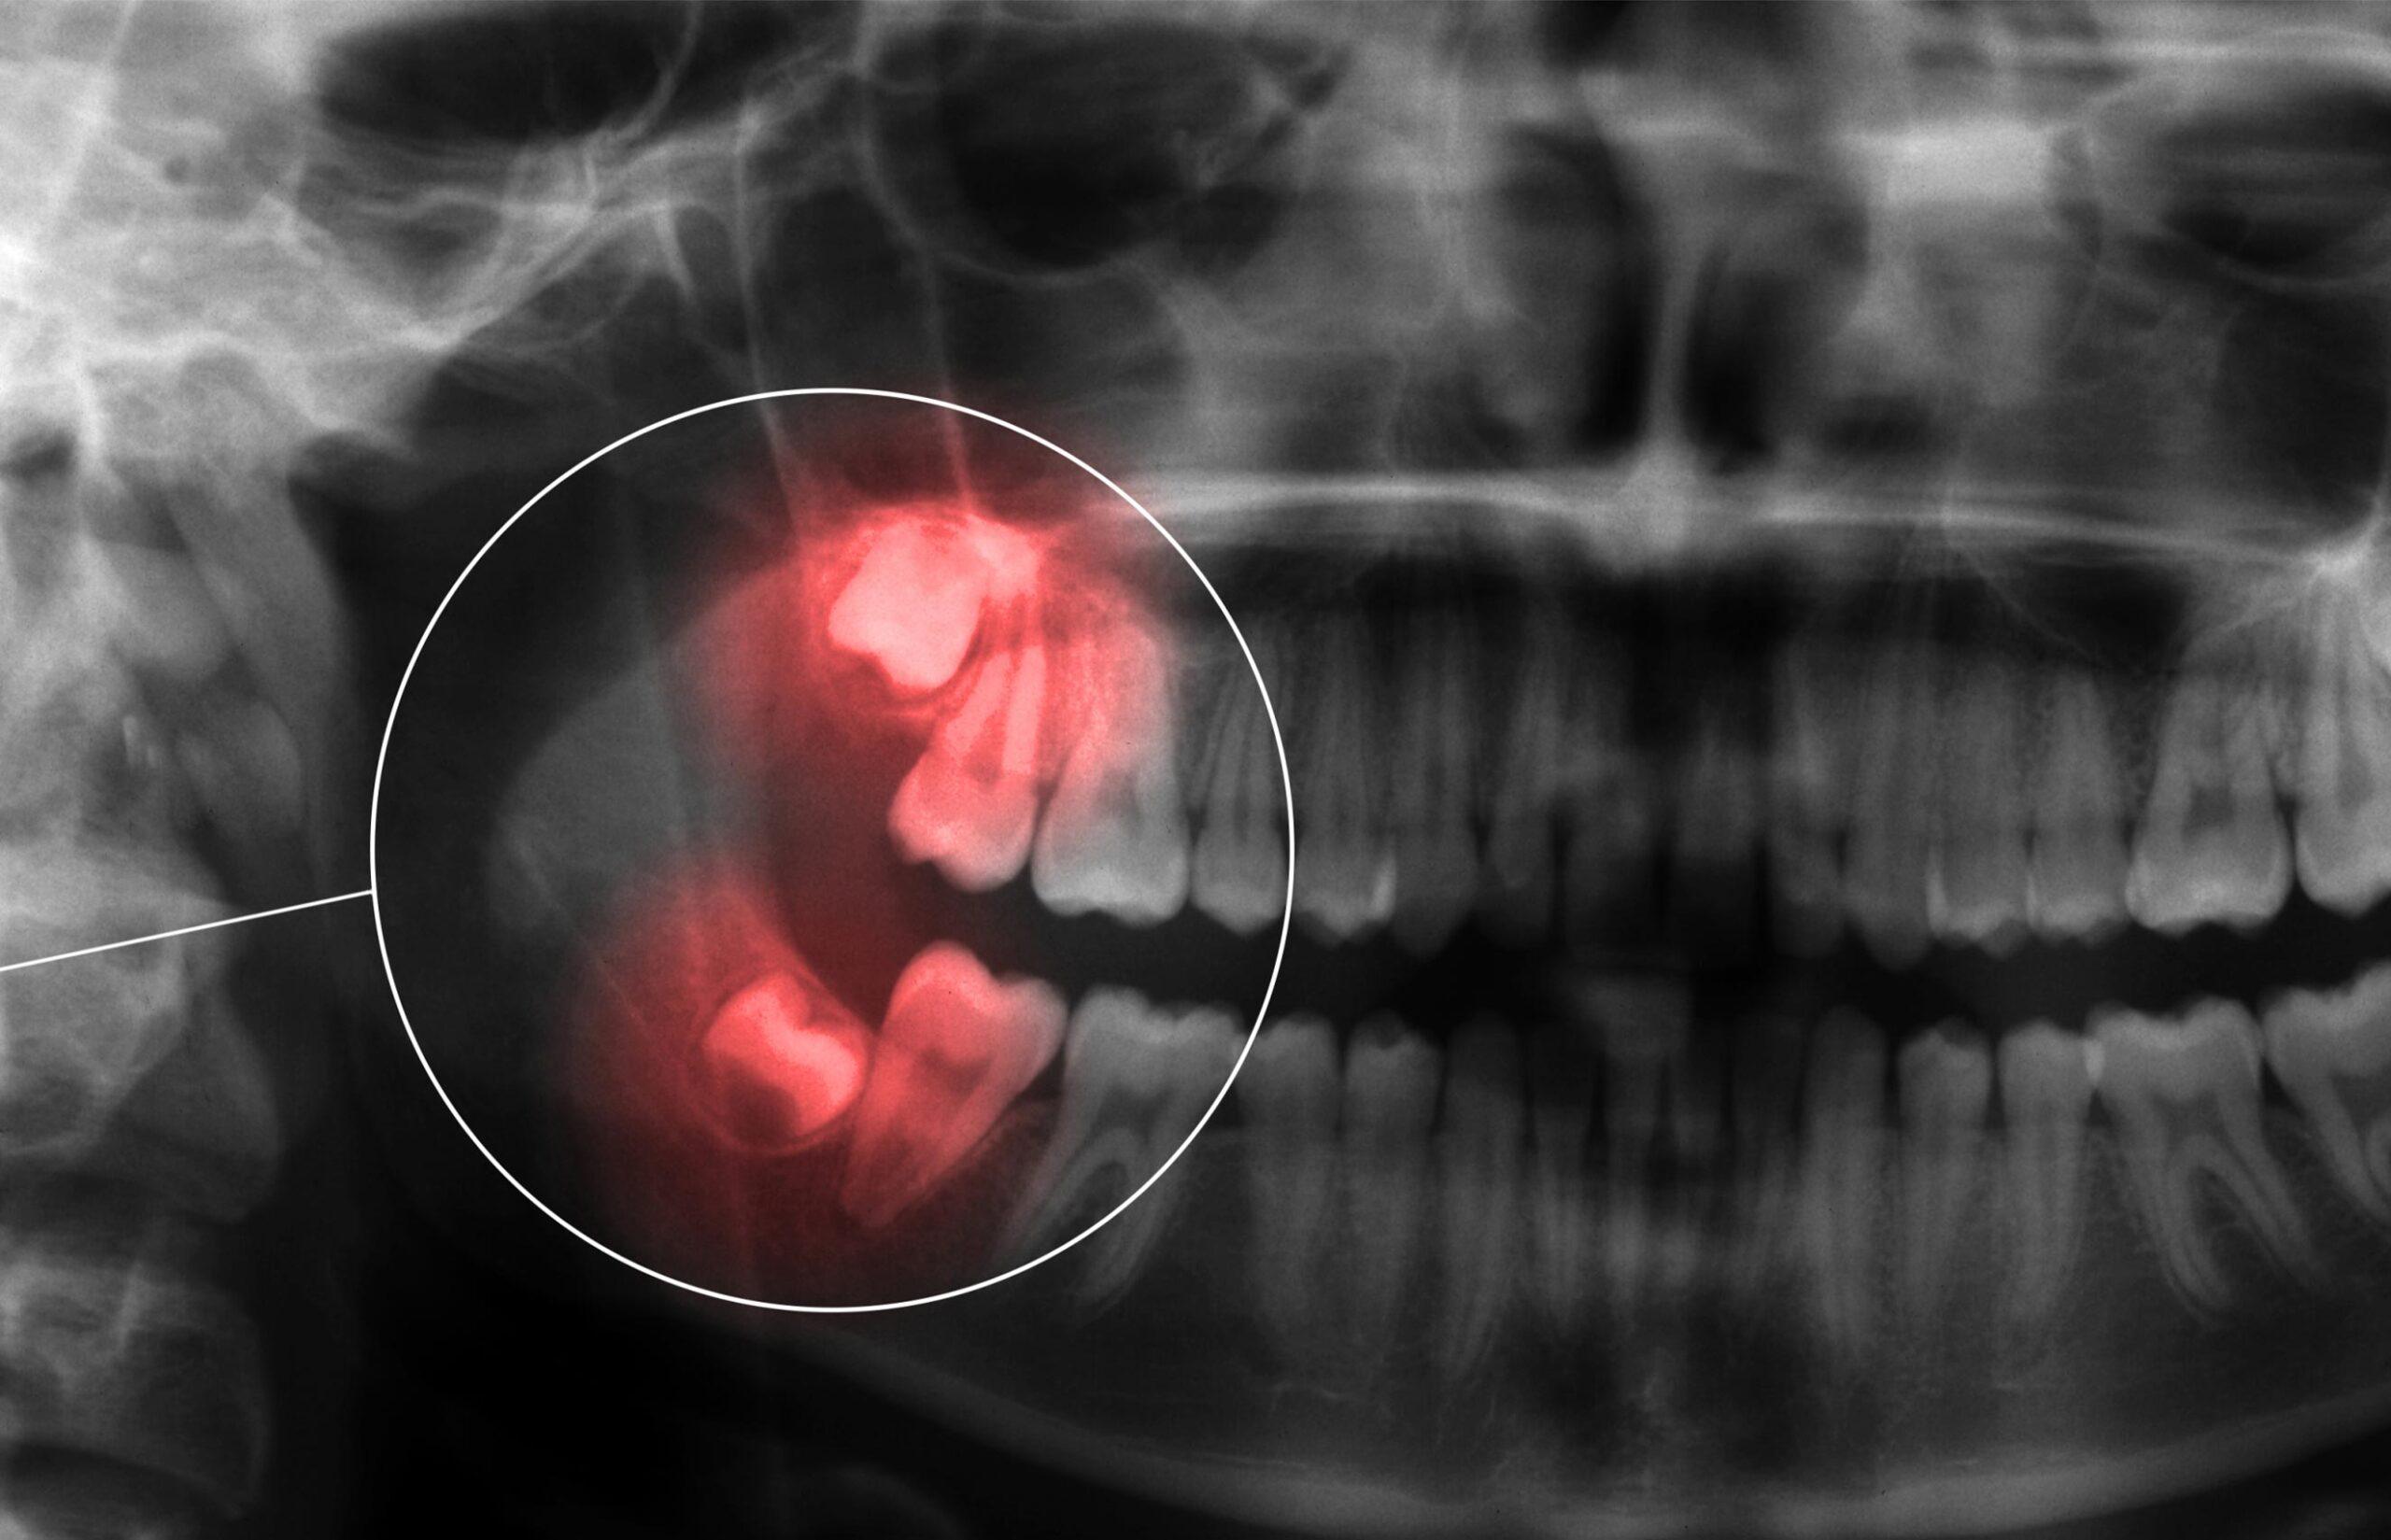

• Growing at an angle, placing pressure on neighbouring teeth or contributing to crowding

• Impacted beneath the gums or bone, which may lead to swelling, discomfort, or infection

What to Expect During a Wisdom Tooth Evaluation

Before recommending removal, our dental team completes a thorough assessment to understand how your wisdom teeth are developing and whether intervention is necessary. Findings and treatment options are reviewed clearly so you can make informed decisions about your care.